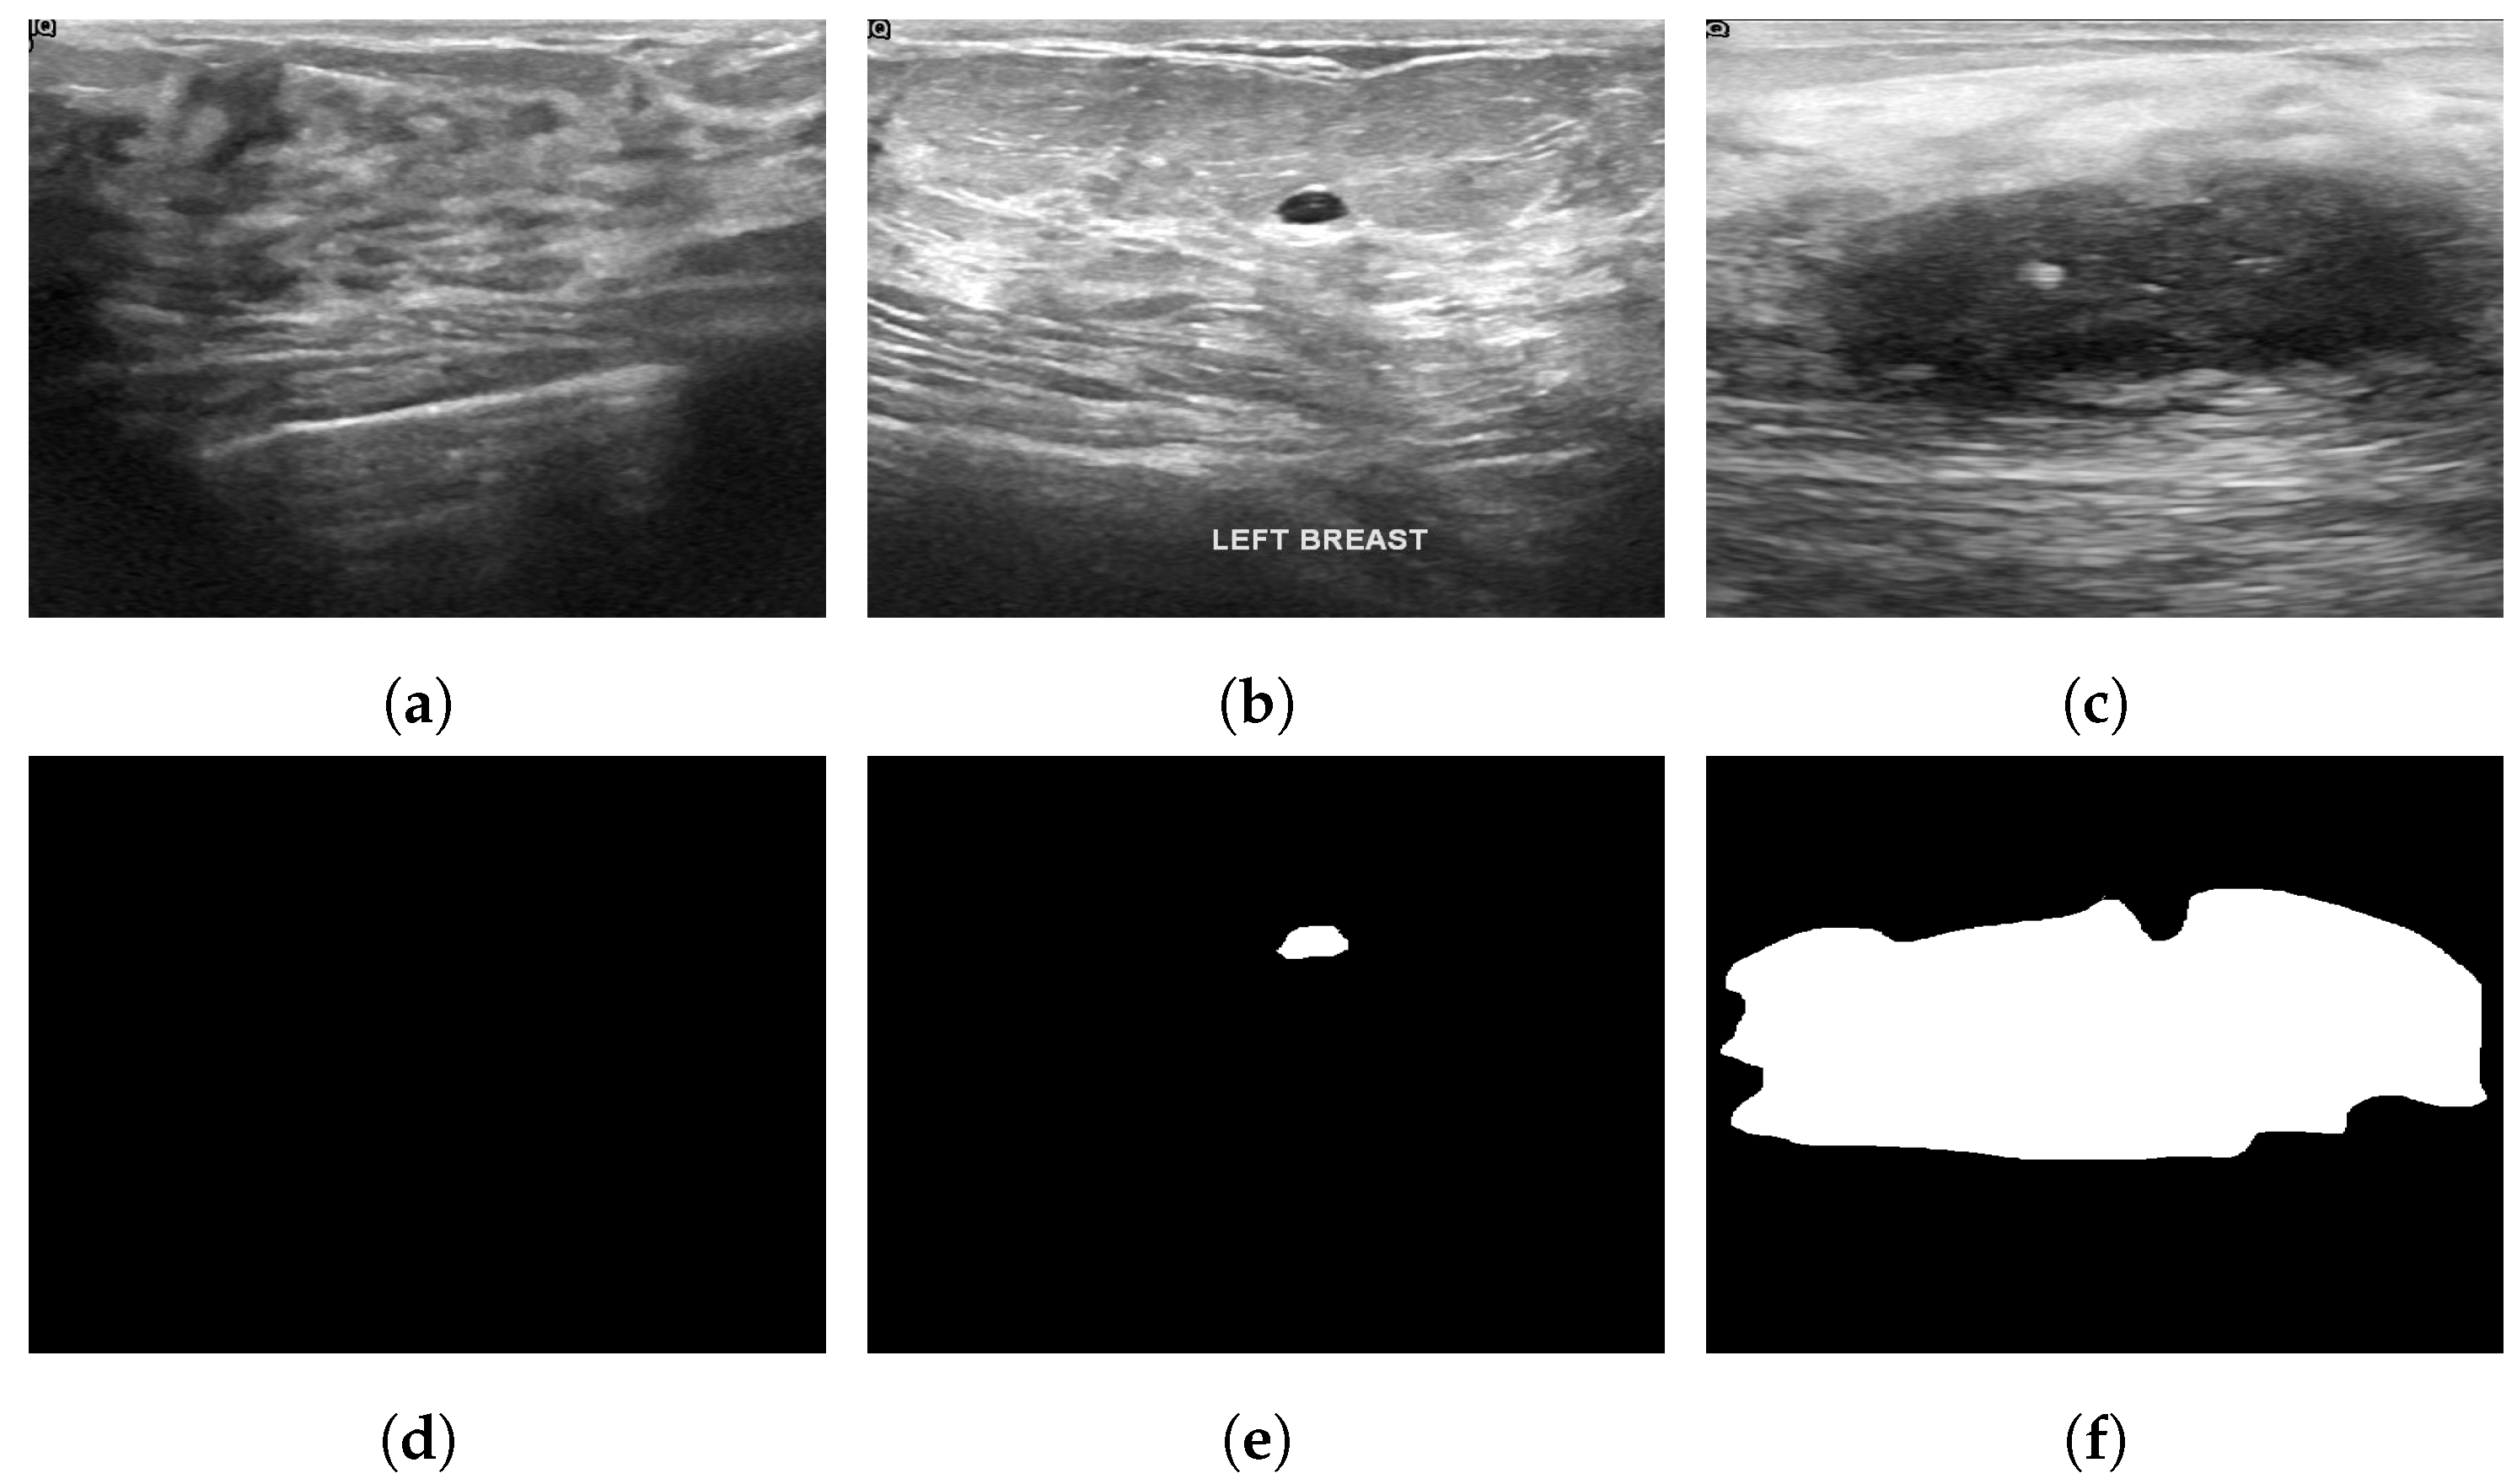

4.3. Ultrasonography